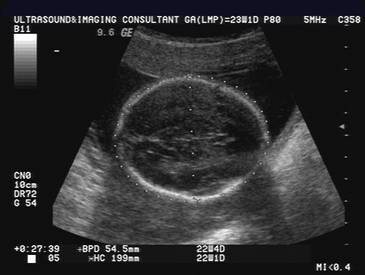

NORMAL CONVEX CONTOUR OF THE FETAL CRANIUM

Ovoid and symmetrical.

Slight flattening of the forehead.

Slight convex bilateral bulging of the parietal eminences.

Brighter and thicker than the falx on the trans-axial view.

Continuity of the calvarium.